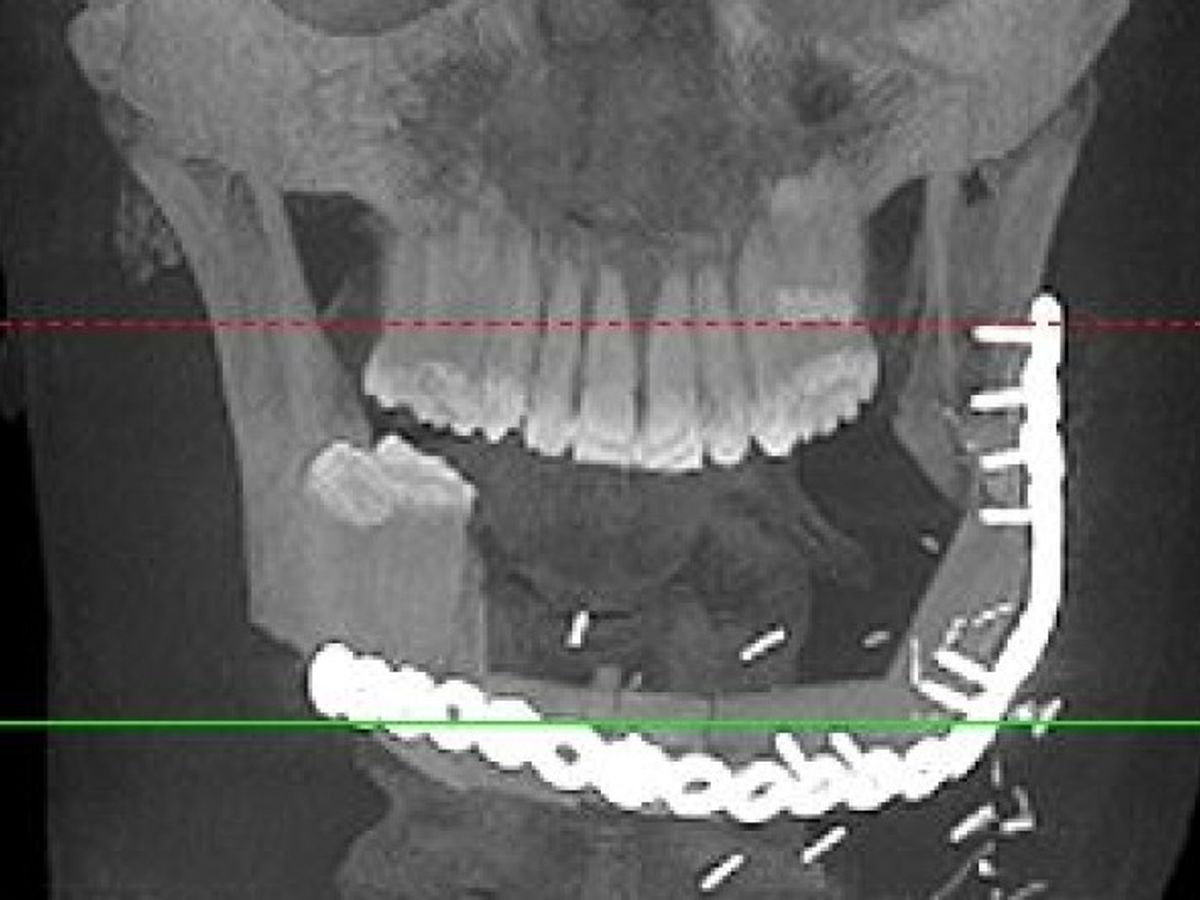

In 2015 my brother Vince was diagnosed with a very rare tumor in his jaw called Ameloblastoma. The diagnosis came after he had been misdiagnosed and treated incorrectly for almost 2 years. Vince was referred to the great doctors at HUP who told him he would need the tumor and 25% of his jaw removed. His insurance denied the surgery and all related medical claims over many months.Fighting with the insurance company led to a delay in care which allowed the tumor to grow and ultimatley caused a surgury requiring the removal of 85% of his jaw, all but two of his bottom teeth and a complete reconstuction of a new jaw in March 2016. This long battle has lead to medical bills adding up to tens of thousands of dollars. He will need 2 more procedures and pay out of pocket for his replacement teeth.Vince needs teeth and help with the bills his insurance company denied. Vince is a great brother, father, son and friend. If you know him, you know he is always there for the people who need him. We have started a non profit called Vincent DiCostanzo's Big Dumb Face Foundation so all donations are tax deductible!! No donation is too small. Thank you!!!